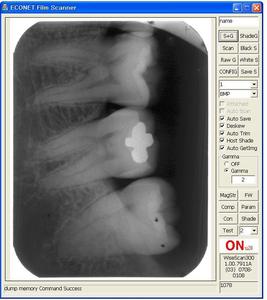

Дентальный снимок

Очень важно подобрать правильное лечение в такой деликатной области как стоматология, где каждое посещение врача вызывает не самые приятные ожидания и эмоции. Большая часть зуба невидима, только 30-40% его находится на поверхности, выступает в полость рта (так называемая коронка). И только рентгеновский снимок позволяет выявить всю картину, отобразить весь зуб целиком.

Существует множество различных видов рентгенологического исследования. Снимки могут быть: Дентальные - показывают небольшой участок – один-два зуба. Панорамные - отображают челюсть (верхнюю, нижнюю) целиком, дают полное представление о состоянии зубов

Дентальные снимки используются в любой момент лечения – до, во время или после него. Они показывают внутреннюю структуру зуба: корневые каналы, их проходимость и заполненность. Так, при неполной пломбировке у пациента могут возникнуть боль и воспаления. Рентгенограмма зуба может быть сделана с введенными корневыми иглами.

По снимку врач быстро определяет все недостатки. Эмаль видна на нем в виде тени, окаймляющей поверхность зуба. Корневые каналы представляют собой четко выраженные полоски. А внутренняя полость зуба (дентин, пульпа) определяется более высоким разрешением.